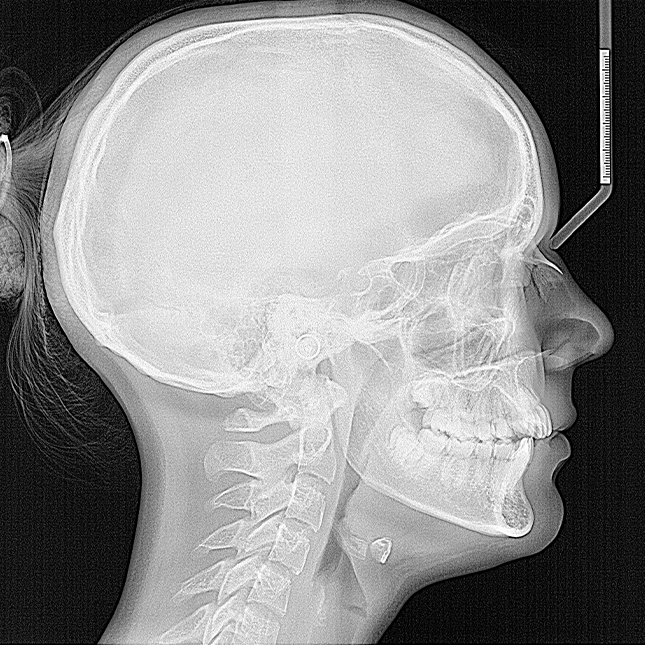

2. Cefalogram (zdjęcie cefalometryczne)

Cefalogram to zdjęcie boczne czaszki wykonane w określonej, powtarzalnej projekcji, gdzie pozycja głowy pacjenta jest stabilizowana przez pozycjoner. To zdjęcie stanowi podstawę dla analizy cefalometrycznej, która jest kluczowa w ortodoncji. Analiza cefalometryczna umożliwia:

•  Diagnostykę wad zgryzu – umożliwia precyzyjne pomiary i określenie, czy wady zgryzu wymagają interwencji ortodontycznej.

•  Ocena stadium wzrostu – pozwala ocenić, w jakim etapie rozwoju znajduje się pacjent, co jest szczególnie ważne w przypadku dzieci i młodzieży.

•  Planowanie leczenia ortodontycznego – zdjęcie stanowi punkt wyjścia do opracowania indywidualnego planu leczenia.

•  Ocena charakteru leczenia – na podstawie zdjęcia można ocenić, czy leczenie będzie zachowawcze, czy wymagane będą bardziej zaawansowane procedury.

Powtarzalność tego badania pozwala na monitorowanie przebiegu leczenia, ocenę postępu wzrostu oraz porównanie zmian w uzyskanych wynikach, co ma kluczowe znaczenie dla skuteczności terapii ortodontycznej. Analiza cefalometryczna pozwala także na ocenę efektywności leczenia operacyjnego i jego ostatecznych rezultatów.

>   Zdjęcie cefalometryczne.